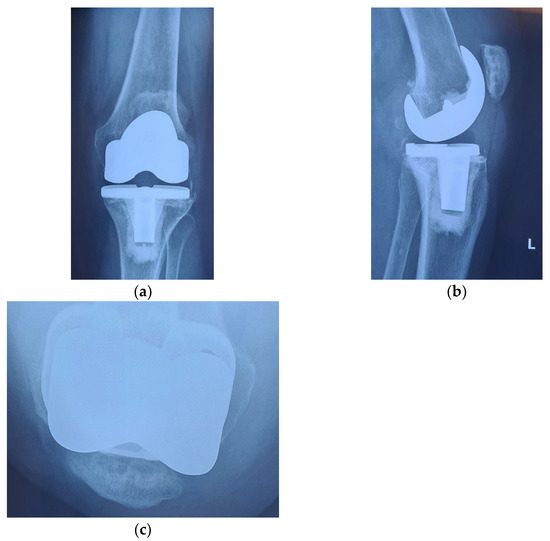

Radiological and clinical follow-up were performed at 6 weeks, 3 months and then 12 months after surgery (Figure 7, Figure 8 and Figure 9).

Figure 9.

12 months after surgery: (a) coronal view, normal centered patella; (b) lateral view, no signs of patellar loosening; (c) axial view, normal centered patella in femoral trochlea.

The clinical evolution of the patient was also satisfactory. The anterior knee pain decreased significantly at 6 weeks after surgery and was absent at 3 months. At the same time, we recorded a significant improvement of the joint function, the episodes of swelling being completely absent. The aspect at 12 months after surgery is shown in Figure 10. The patient can easily achieve 120 degrees flexion without pain, full extension without joint swelling and is able at climbing stairs and get up from a chair, without pain.